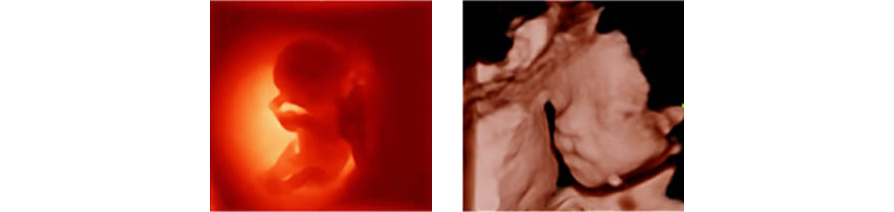

iLive

Al integrar un algoritmo de proyecciĂłn de rayos con una nueva modalidad de iluminaciĂłn virtual, iLive genera imĂĄgenes increĂblemente reales del feto con una piel de apariencia humana.

Smart Face

El nuevo Z50 proporciona una optimizaciĂłn rĂĄpida e inteligente del rostro del feto con una simple operaciĂłn de un solo toque. Puede eliminar de forma inmediata las oclusiones en los datos de volumen, excluir el ruido no deseado y generar una visiĂłn Ăłptima del rostro fetal con un mĂnimo de esfuerzo.